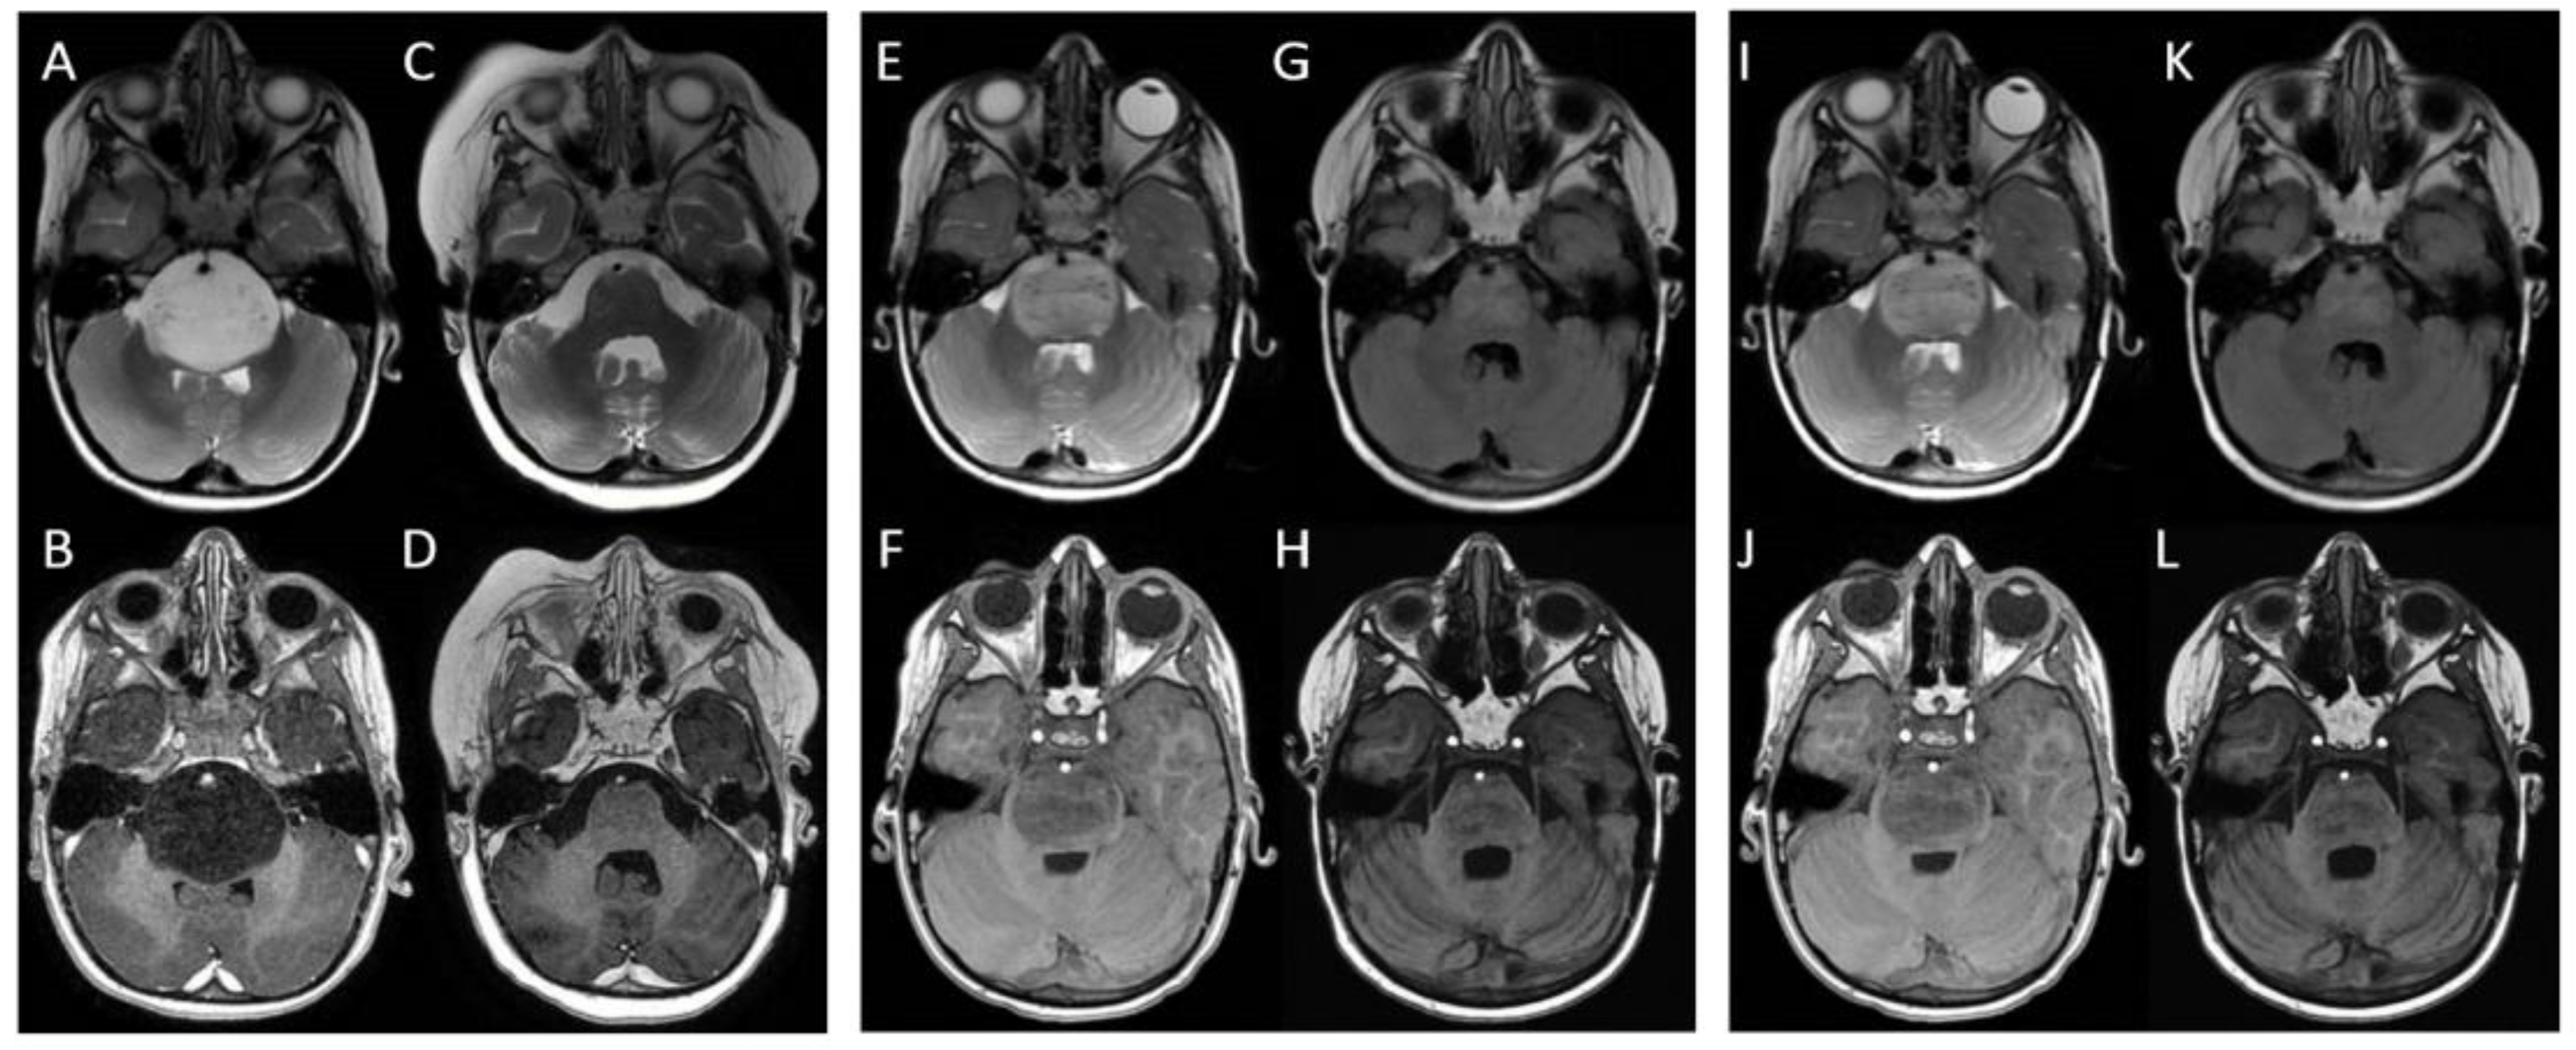

| Child n. 1 | 9 months | 6 months | 24 months |

| Child n. 2 | 6 months | 4 months | 18 months |

| Child n. 3 | 6 months | 3 months | 17 months |

| Median value ± standard deviation | 7 ± 1.7 months | 4.3 ± 1.5 months | 19.6 ± 3.7 months |